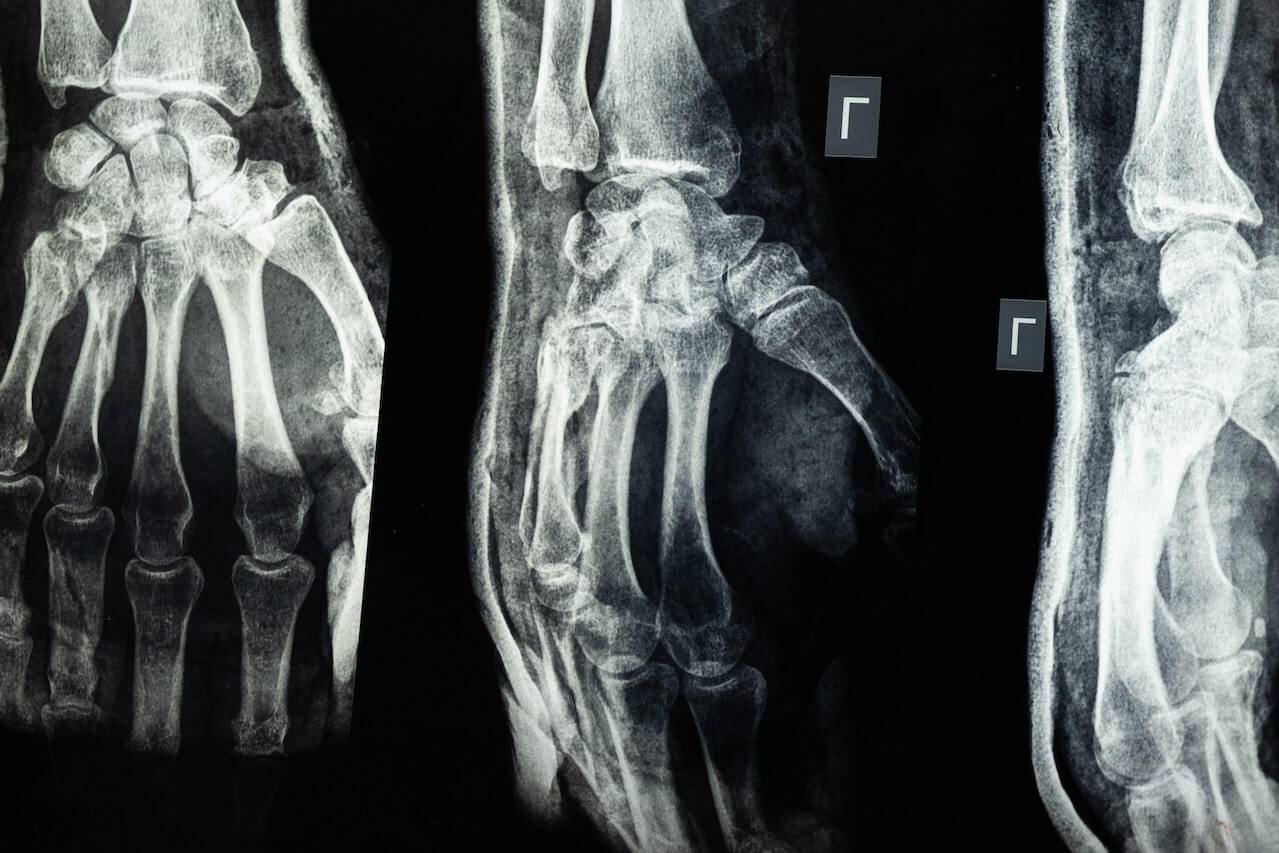

Fin quando non diventerà più rigido e duro, il callo osseo non sarà visibile in radiografia.

La terza fase della guarigione di una frattura è quella in cui il callo osseo diventa più duro e forte. Questa fase ha inizio verso le 6 settimane dopo l’infortunio. Il callo “subisce un processo di rimodellamento”, l’osso si rinsalda e riacquista la forma originale.